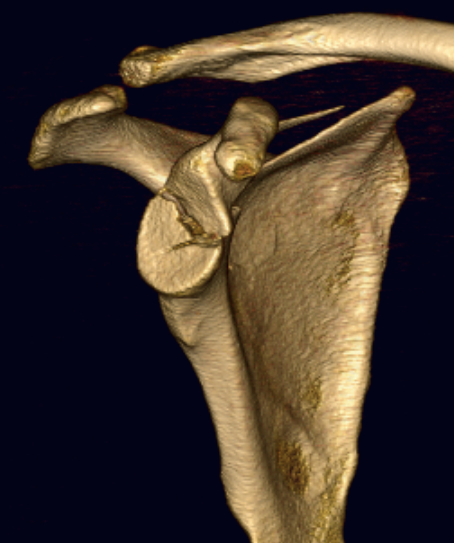

Case 1

- > 1 cm medial displacement

- ORIF via posterior / modified Judet approach